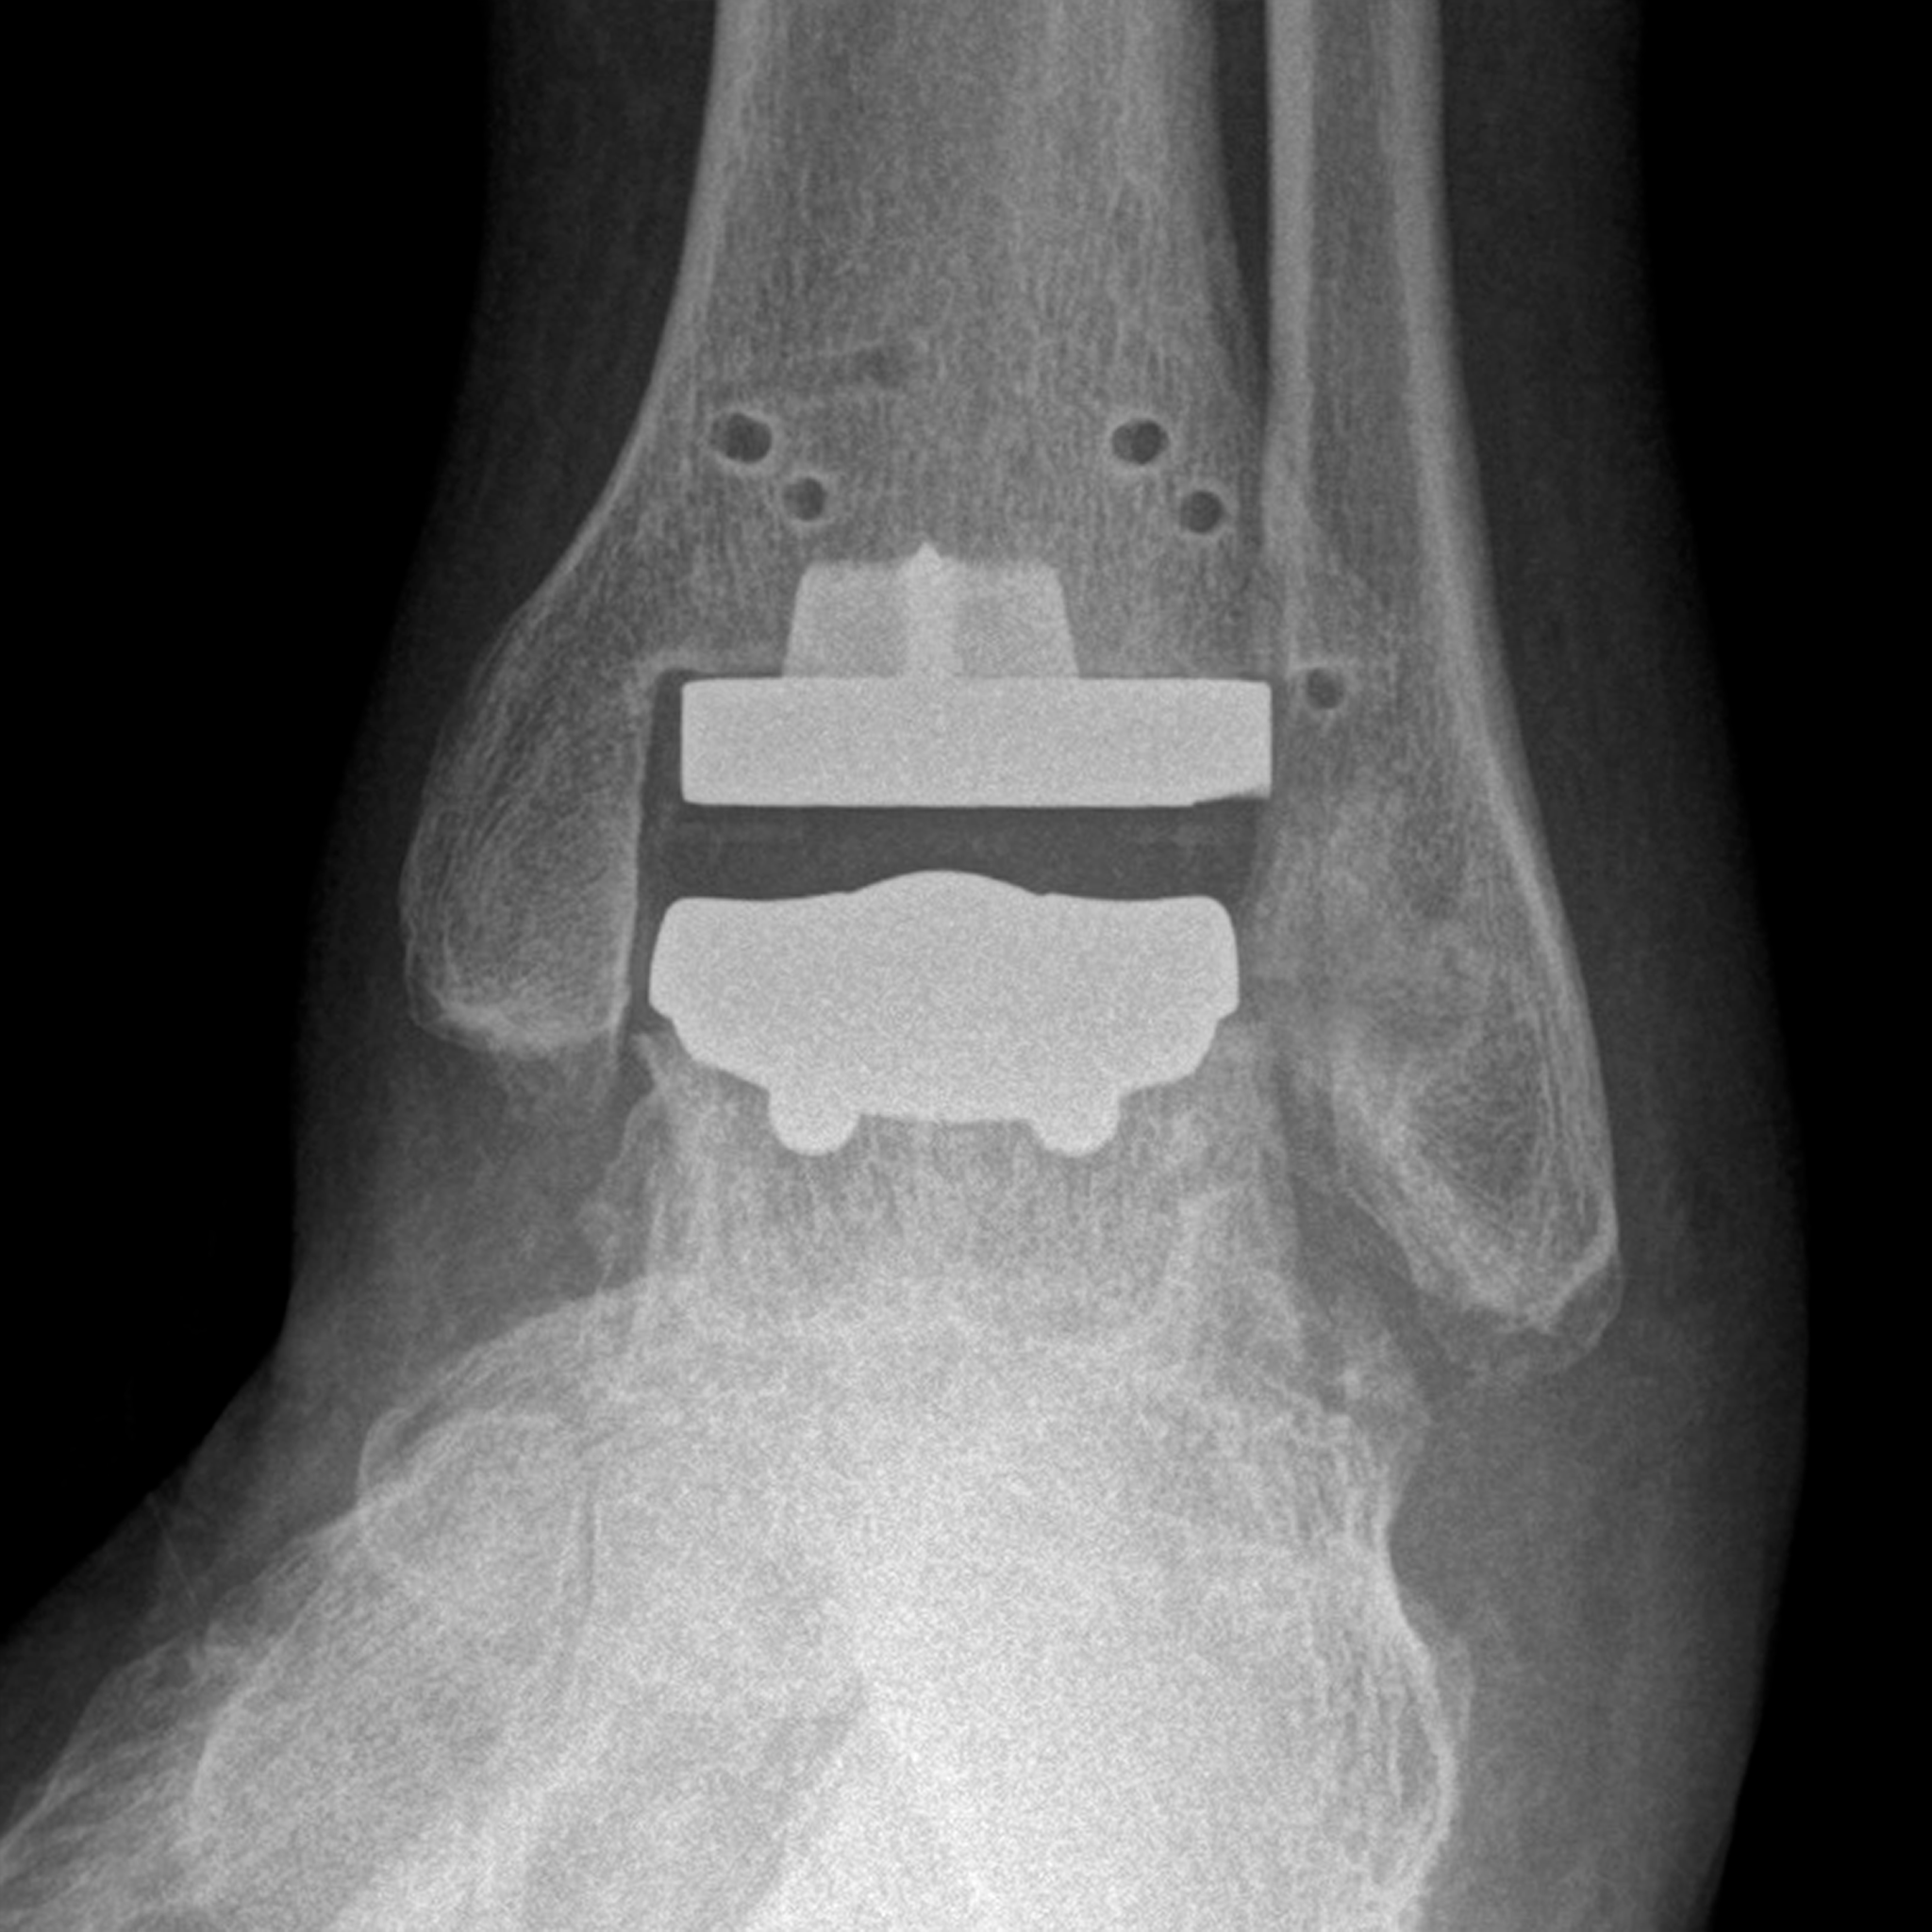

Bei der Sprunggelenk-Endoprothetik hat sich in den letzten Jahren sowohl die Implantat-Qualität als auch die Präzision der Implantation deutlich verbessert. Eine bessere präoperative Planung, bessere Instrumente oder seit neuestem auch Patientenspezifische Instrumente (sogenannte PSI) erlauben es, das Implantat mit einer bisher nicht dagewesenen Genauigkeit einzusetzen. Bei den Patientenspezifischen Instrumenten wird auf Basis von CT-Bildern die OP-Planung im Vorfeld des Eingriffs am Computer durchgeführt (Abb. 1).

Auf Basis der Planung werden dann passgenaue Sägeschablonen produziert, die wie ein Puzzleteil exakt auf den Knochen des Patienten passen und damit die Position des Implantats entsprechend der präoperativen Planung vorgeben (Abb. 2).

Neben der Genauigkeit ist die verkürzte Operationszeit ein weiterer Vorteil des Verfahrens. Die Röntgenbilder nach (Abb. 3 und 4) zeigen eine solche Situation wenige Tage einer Prothesenimplantation am Sprunggelenk.